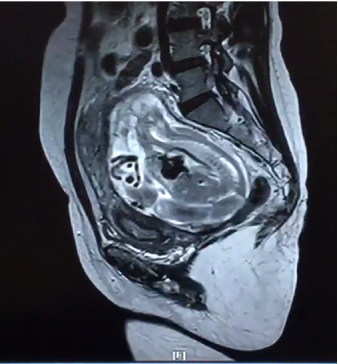

2月24日,我院产科、泌尿外科、麻醉手术科、胃肠外科、输血科等多学科合作成功救治一名腹腔妊娠特殊患者。这是我院多学科合作战胜疑难杂症的又一成功案例。近年来,作为三级甲等综合财神捕鱼 ,财神捕鱼 始终坚持以患者为中心,充分发挥综合财神捕鱼 的优势,积极探索研究,持续加强学科建设,不断拓展多学科合作的广度和深度,利用多学科合作为人民群众解决了很多疑难杂症,用实际行动巩固脱贫攻坚成果,助力乡村振兴,为维护人民群众的健康持续奋斗。